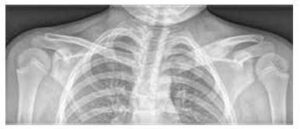

Slika br. 1

Palmoplantarna pustuloza kod pacijenta s CRMO-om

Slika br. 3

Zaglavljenje i osteolitičke lezije medijalnog kraja lijeve ključne kosti i edem mekih tkiva na rendgenskoj snimci